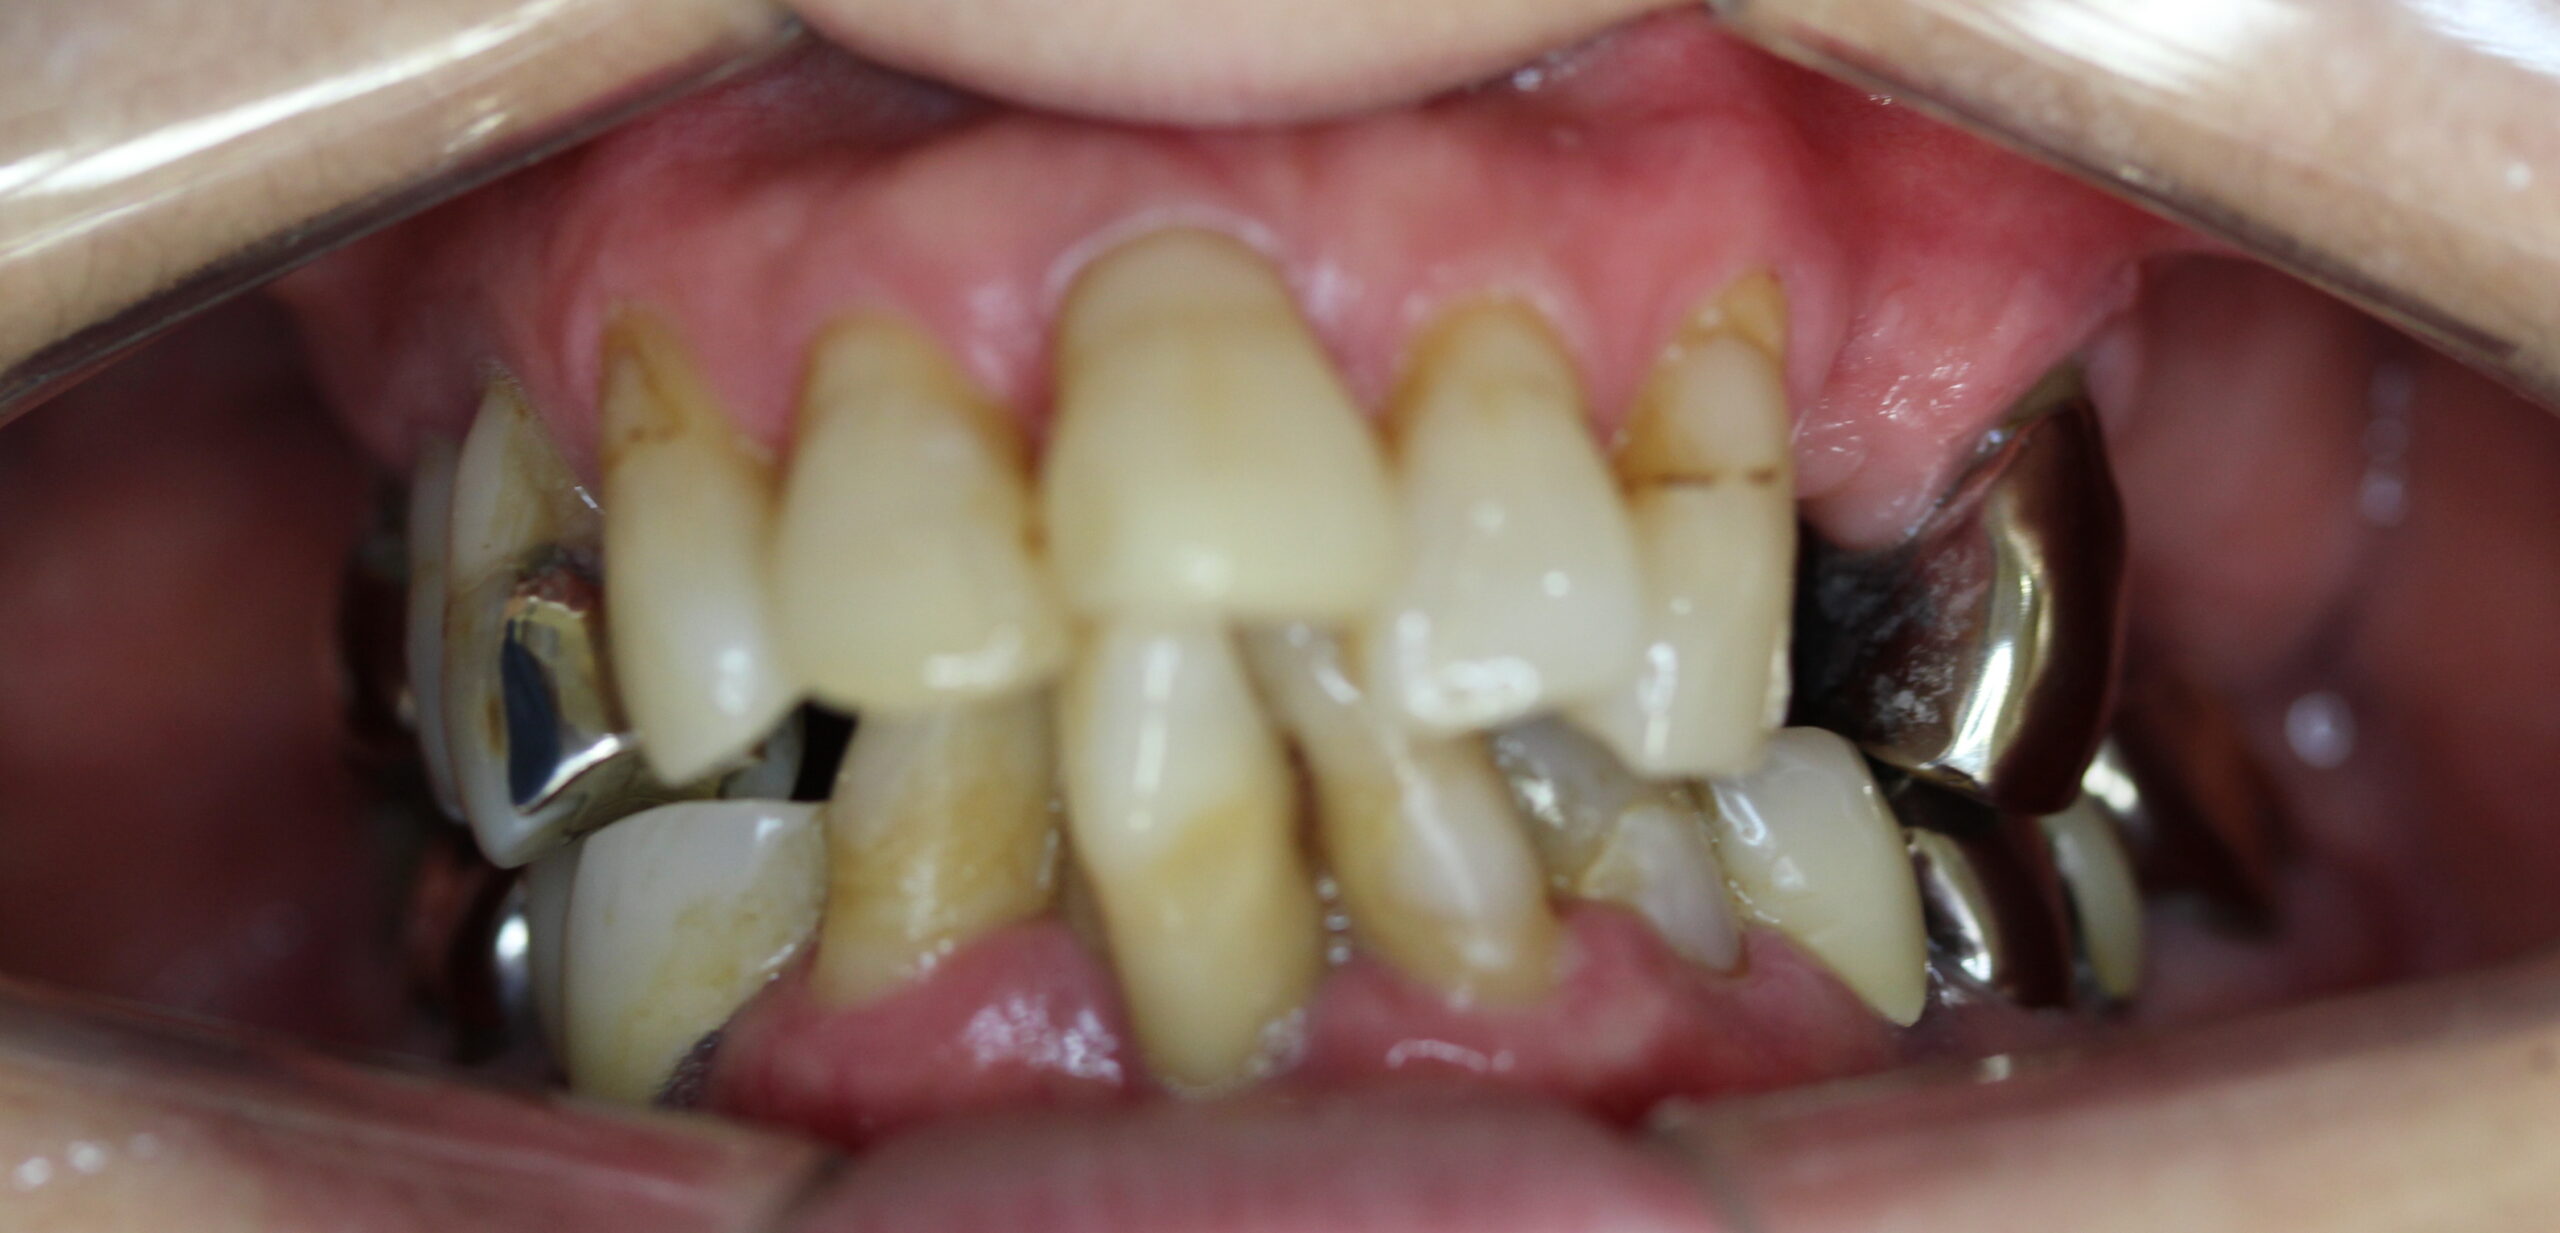

60代女性。歯がぐらついて噛めないので入れ歯を作り直したい。

入れ歯でちゃんと噛めないので新しく作り直したい。

上顎はコーヌステレスコープ、下顎はレジリエンツテレスコープにて治療を行なった。

【治療前】